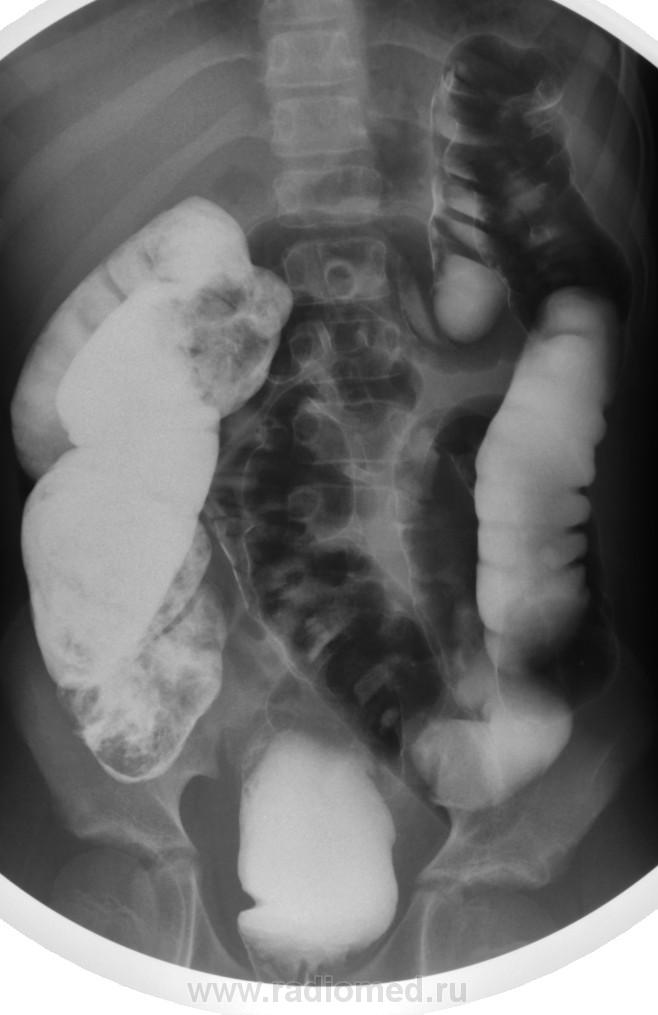

Долихосигма, и плохо очищенная толстая кишка. В детской патологии не силён.

Долихомегасигма, я б сказала, что объясняет клинику запоров. Впрочем, вся кишка расширена. Зоны аганглиоза не видно, на Гиршпрунга не похоже. Селезеночный изгиб не показан адекватно, так что со снимками лежа судить о наличии болезни Пайра проблематично, да и клиники не дано, а жаль.